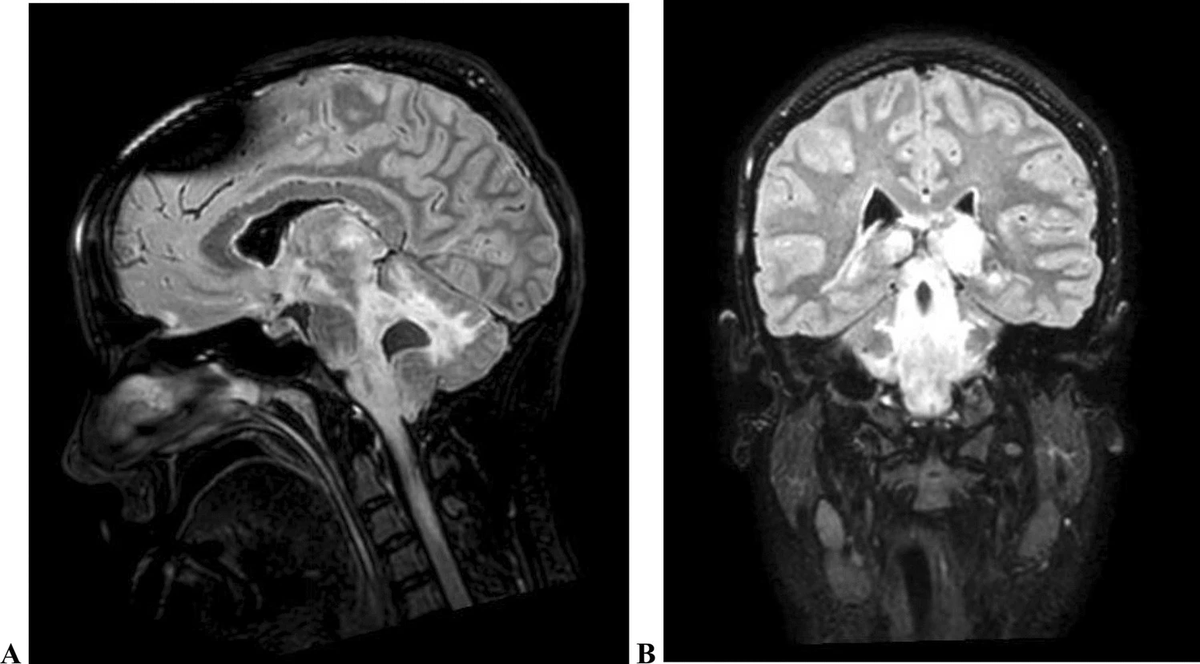

👧A 14-year-old girl presents with progressive right-sided hemiparesis over 4 months. No fever, weight loss, or lymphadenopathy. Exam: mild dysphasia, right hemiparesis, Babinski positive. 👨‍⚕️What would be your differential?

👧A 14-year-old girl presents with progressive right-sided hemiparesis over 4 months. No fever, weight loss, or lymphadenopathy. Exam: mild dysphasia, right hemiparesis, Babinski positive.

👨‍⚕️What would be your differential?